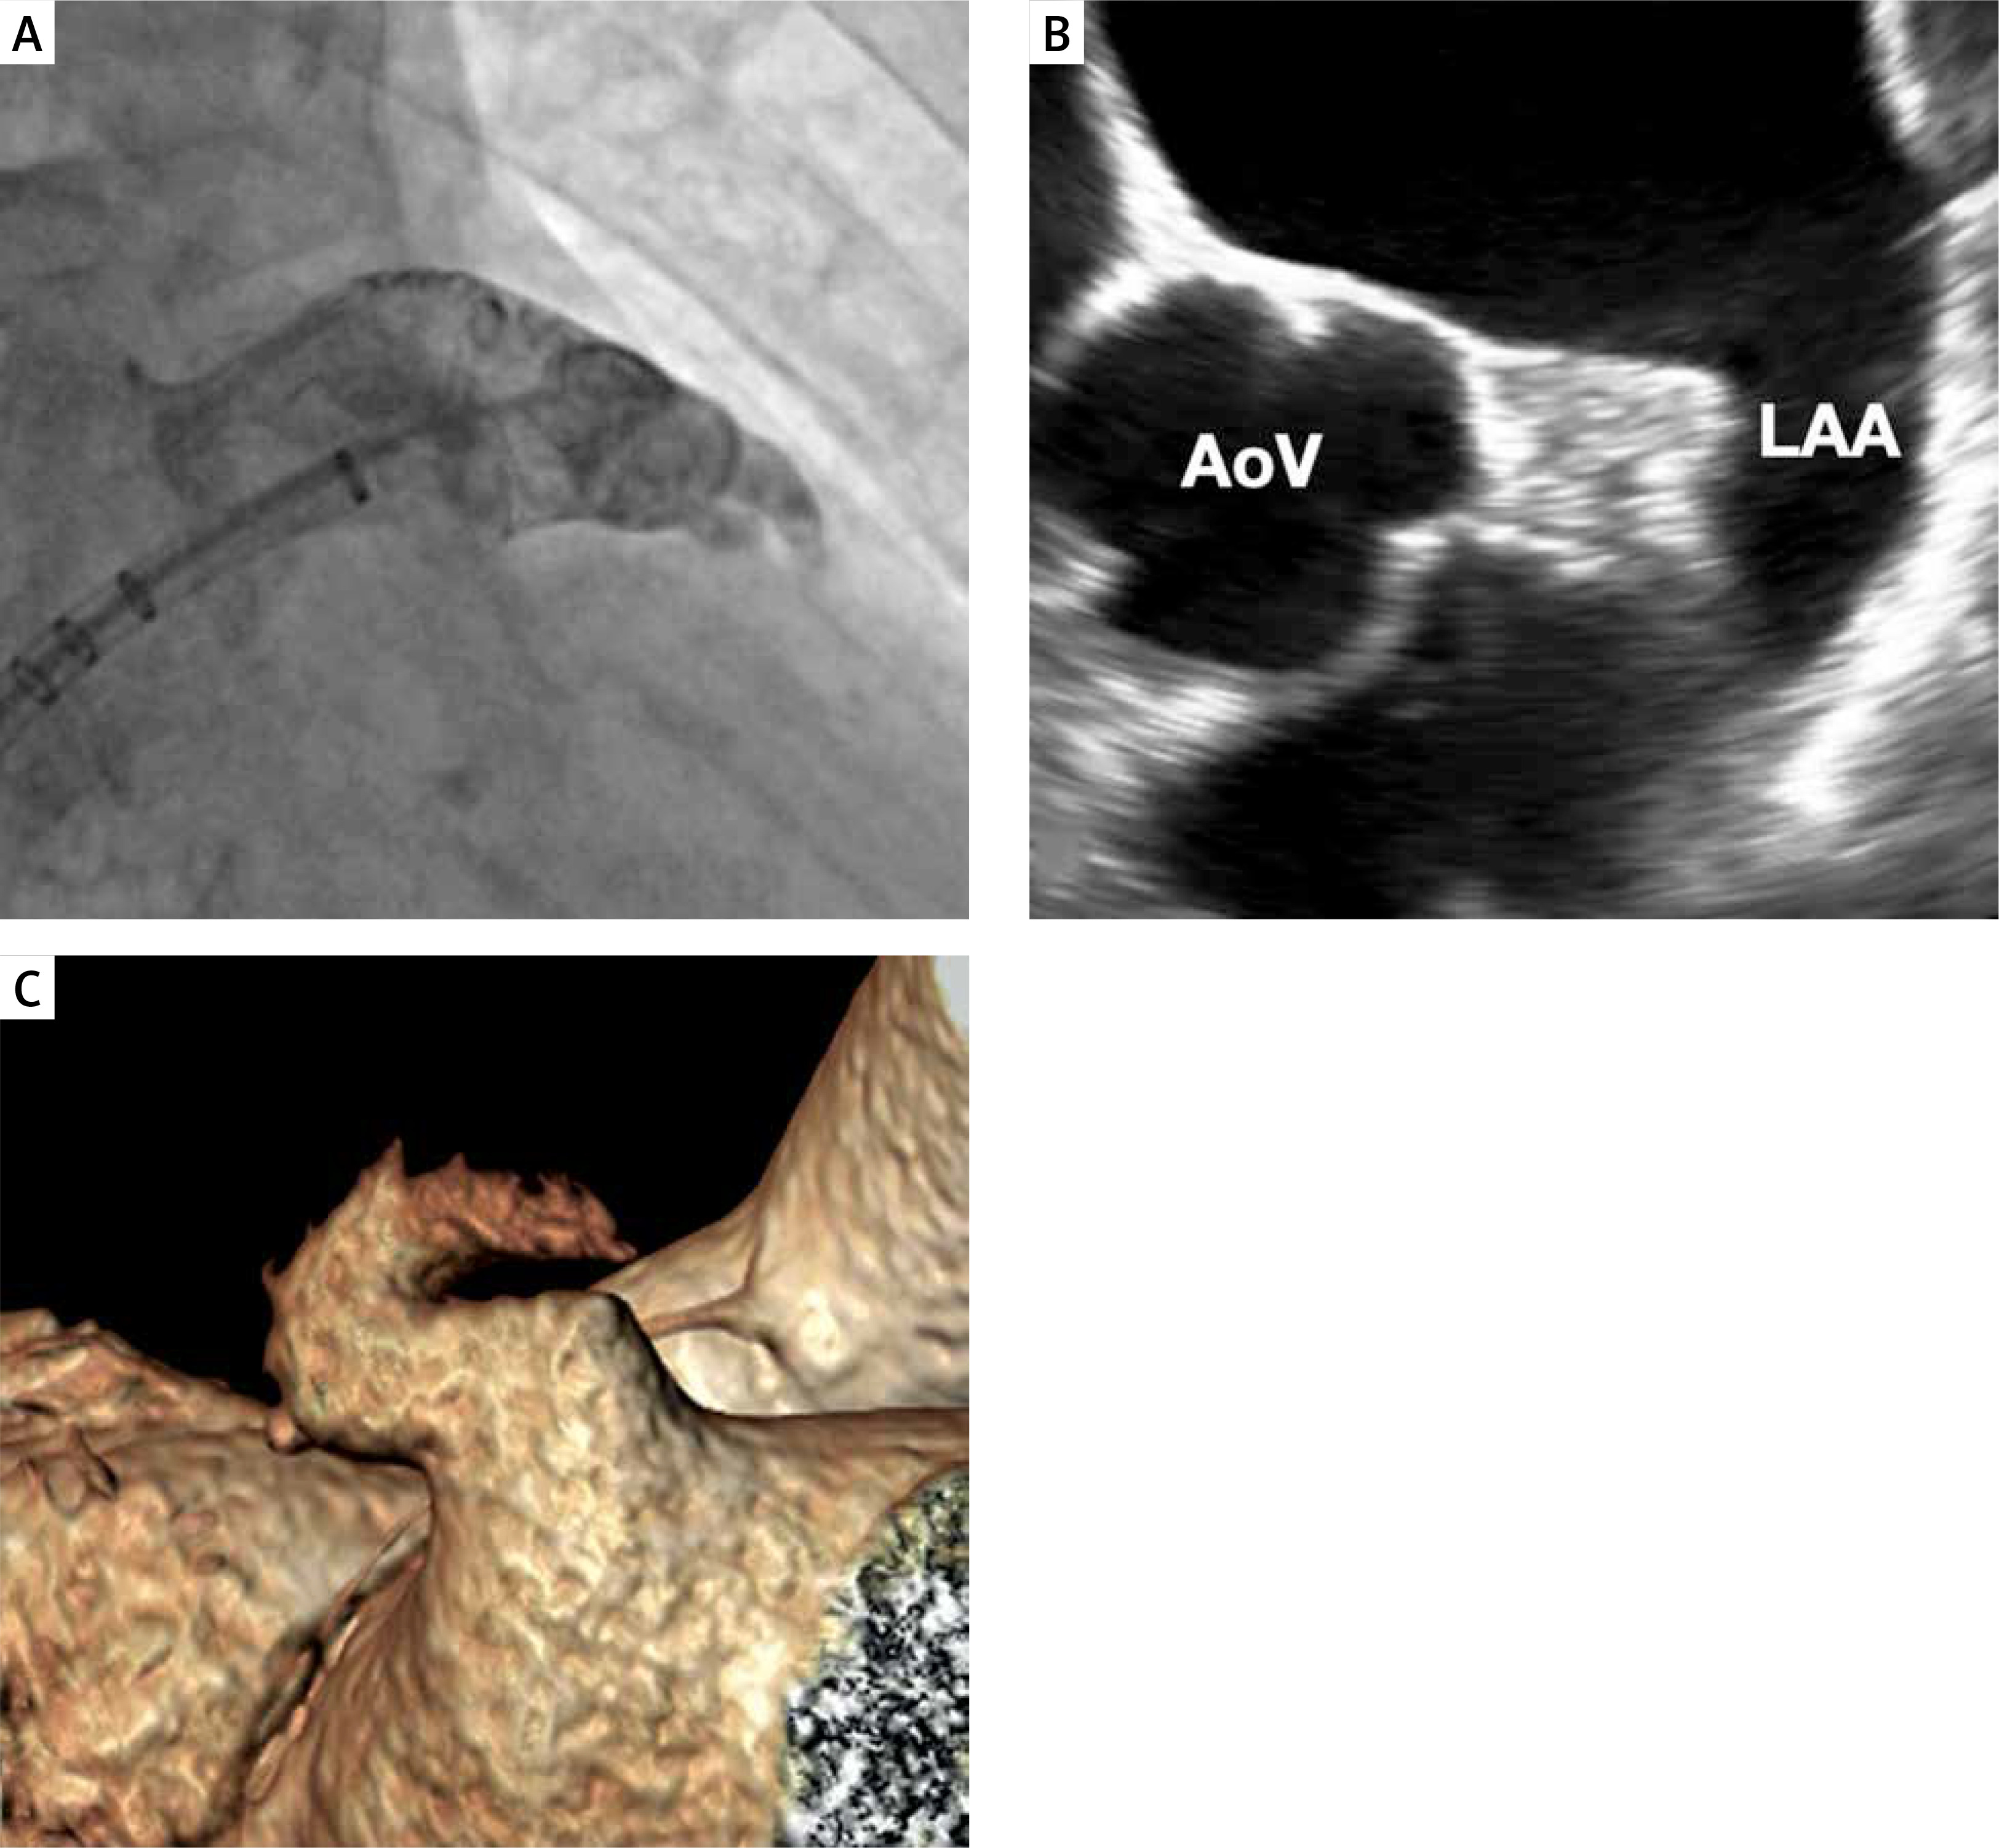

DRT is one of the most concerning complications after successful Watchman device implantation that can be detected by TEE (Figure 4) or CT. In the PROTECT-AF trial the rate of DRT was 4.2% [17]. However, in 2018 Dukkipati et al. published cumulative data regarding DRT incidence in PROTECT AF, PREVAIL, and their continuous access registries [43]. After a mean follow-up time of 4.1 years, the rate of DRT was 3.74%. The analysis of patients with DRT revealed that they were at higher thromboembolic risk assessed with the CHA2DS2-VASc score, were more likely in permanent atrial fibrillation, had a history of TIA or stroke, larger LAA, and had lower ejection fraction (EF). The risk of stroke or systemic embolism was 3.55-fold higher in patients with DRT. In the EWOLUTION registry, at 2-year follow-up DRT was observed in 34 (4.1%) cases among 835 patients with imaging of the LAA after a median time of 54 days (IQR: 41–111 days) [44]. Thirty-one incidents of DRT were observed at the first follow-up imaging usually within 90 days after the procedure. DRT occurred irrespective of the type of the post-LAAC antithrombotic regimen. Patients with DRT more often had non-paroxysmal AF, evidence of spontaneous echo contrast, and a larger ostium diameter of the LAA [45]. Overall, no significant differences in rate of thromboembolic events were observed in patients with or without DRT (1.7 vs. 2.2%/year, p = 0.8). In a prospective registry with the second-generation Watchman FLX device, at 1 year DRT was detected in 7 (1.7%) patients with 4 cases discovered during scheduled follow-up visits [28]. In the real-world registry of Watchman FLX, DRT was observed in 2.4% of cases through 1 year of follow-up and all were detected during routine imaging [30].

Figure 4

Device-related thrombus on Watchman 2.5 device. The arrow indicates a thrombus on the surface of the implanted device